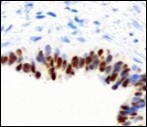

Alternatively, cutaneous ciliated cyst can be lined by non ciliated cuboidal or columnar epithelium with intermingled intercalated, dark or round peg cells. Foci of squamous metaplasia can be occasionally exemplified in the adherent epithelium whereas mucinous cells or apocrine-like features are exceptional 6, 8. Figure 1, Figure 2, Figure 3, Figure 4, Figure 5, Figure 6, Figure 7, Figure 8, Figure 9, Figure 10, Figure 11, Figure 12. 11, 12, 13, 14, 15, 16, 17, 18, 19.

Figure 10.Cutaneous ciliated cyst with nuclear immune reactivity to progesterone receptors (18).

Epithelium of cutaneous ciliated cyst is immune reactive for pan cytokeratin (CKae1/ae3) antigens, epithelial membrane antigen (EMA), oestrogen receptors (ER), progesterone receptors (PR), Wilm’s tumour protein (WT-1) and paired box gene 8 (PAX8). Immune non reactivity is cogitated for S100, smooth muscle actin (SMA), carcino-embryonic antigen (CEA), desmin, thyroid transcription factor(TTF1), p63 and glial fibrillary acidic protein (GFAP).

Smooth muscle actin (SMA) is immune non reactive, thereby suggesting an absence of smooth muscle within the cyst wall. Intense immune reactivity can be cogitated within epithelial nuclei for oestrogen receptors (ER) and progesterone receptors (PR). Aforesaid immune reactions are indicative of Mullerian origin of cutaneous ciliated cyst.

Cutaneous ciliated cyst demonstrates immune reactivity to Dyein, akin to the reaction elicited in normal fallopian epithelium. Nevertheless, atypical locations of cutaneous ciliated cyst or those arising in males are immune non- reactive with oestrogen receptors (ER) and progesterone receptors (PR) on account of enunciated eccrine glandular epithelium. However, particular instances are immune reactive with carcinoembryonic antigen (CEA), p63, S100 and gross cystic fluid disease protein (GCFDP-15) 8, 9.